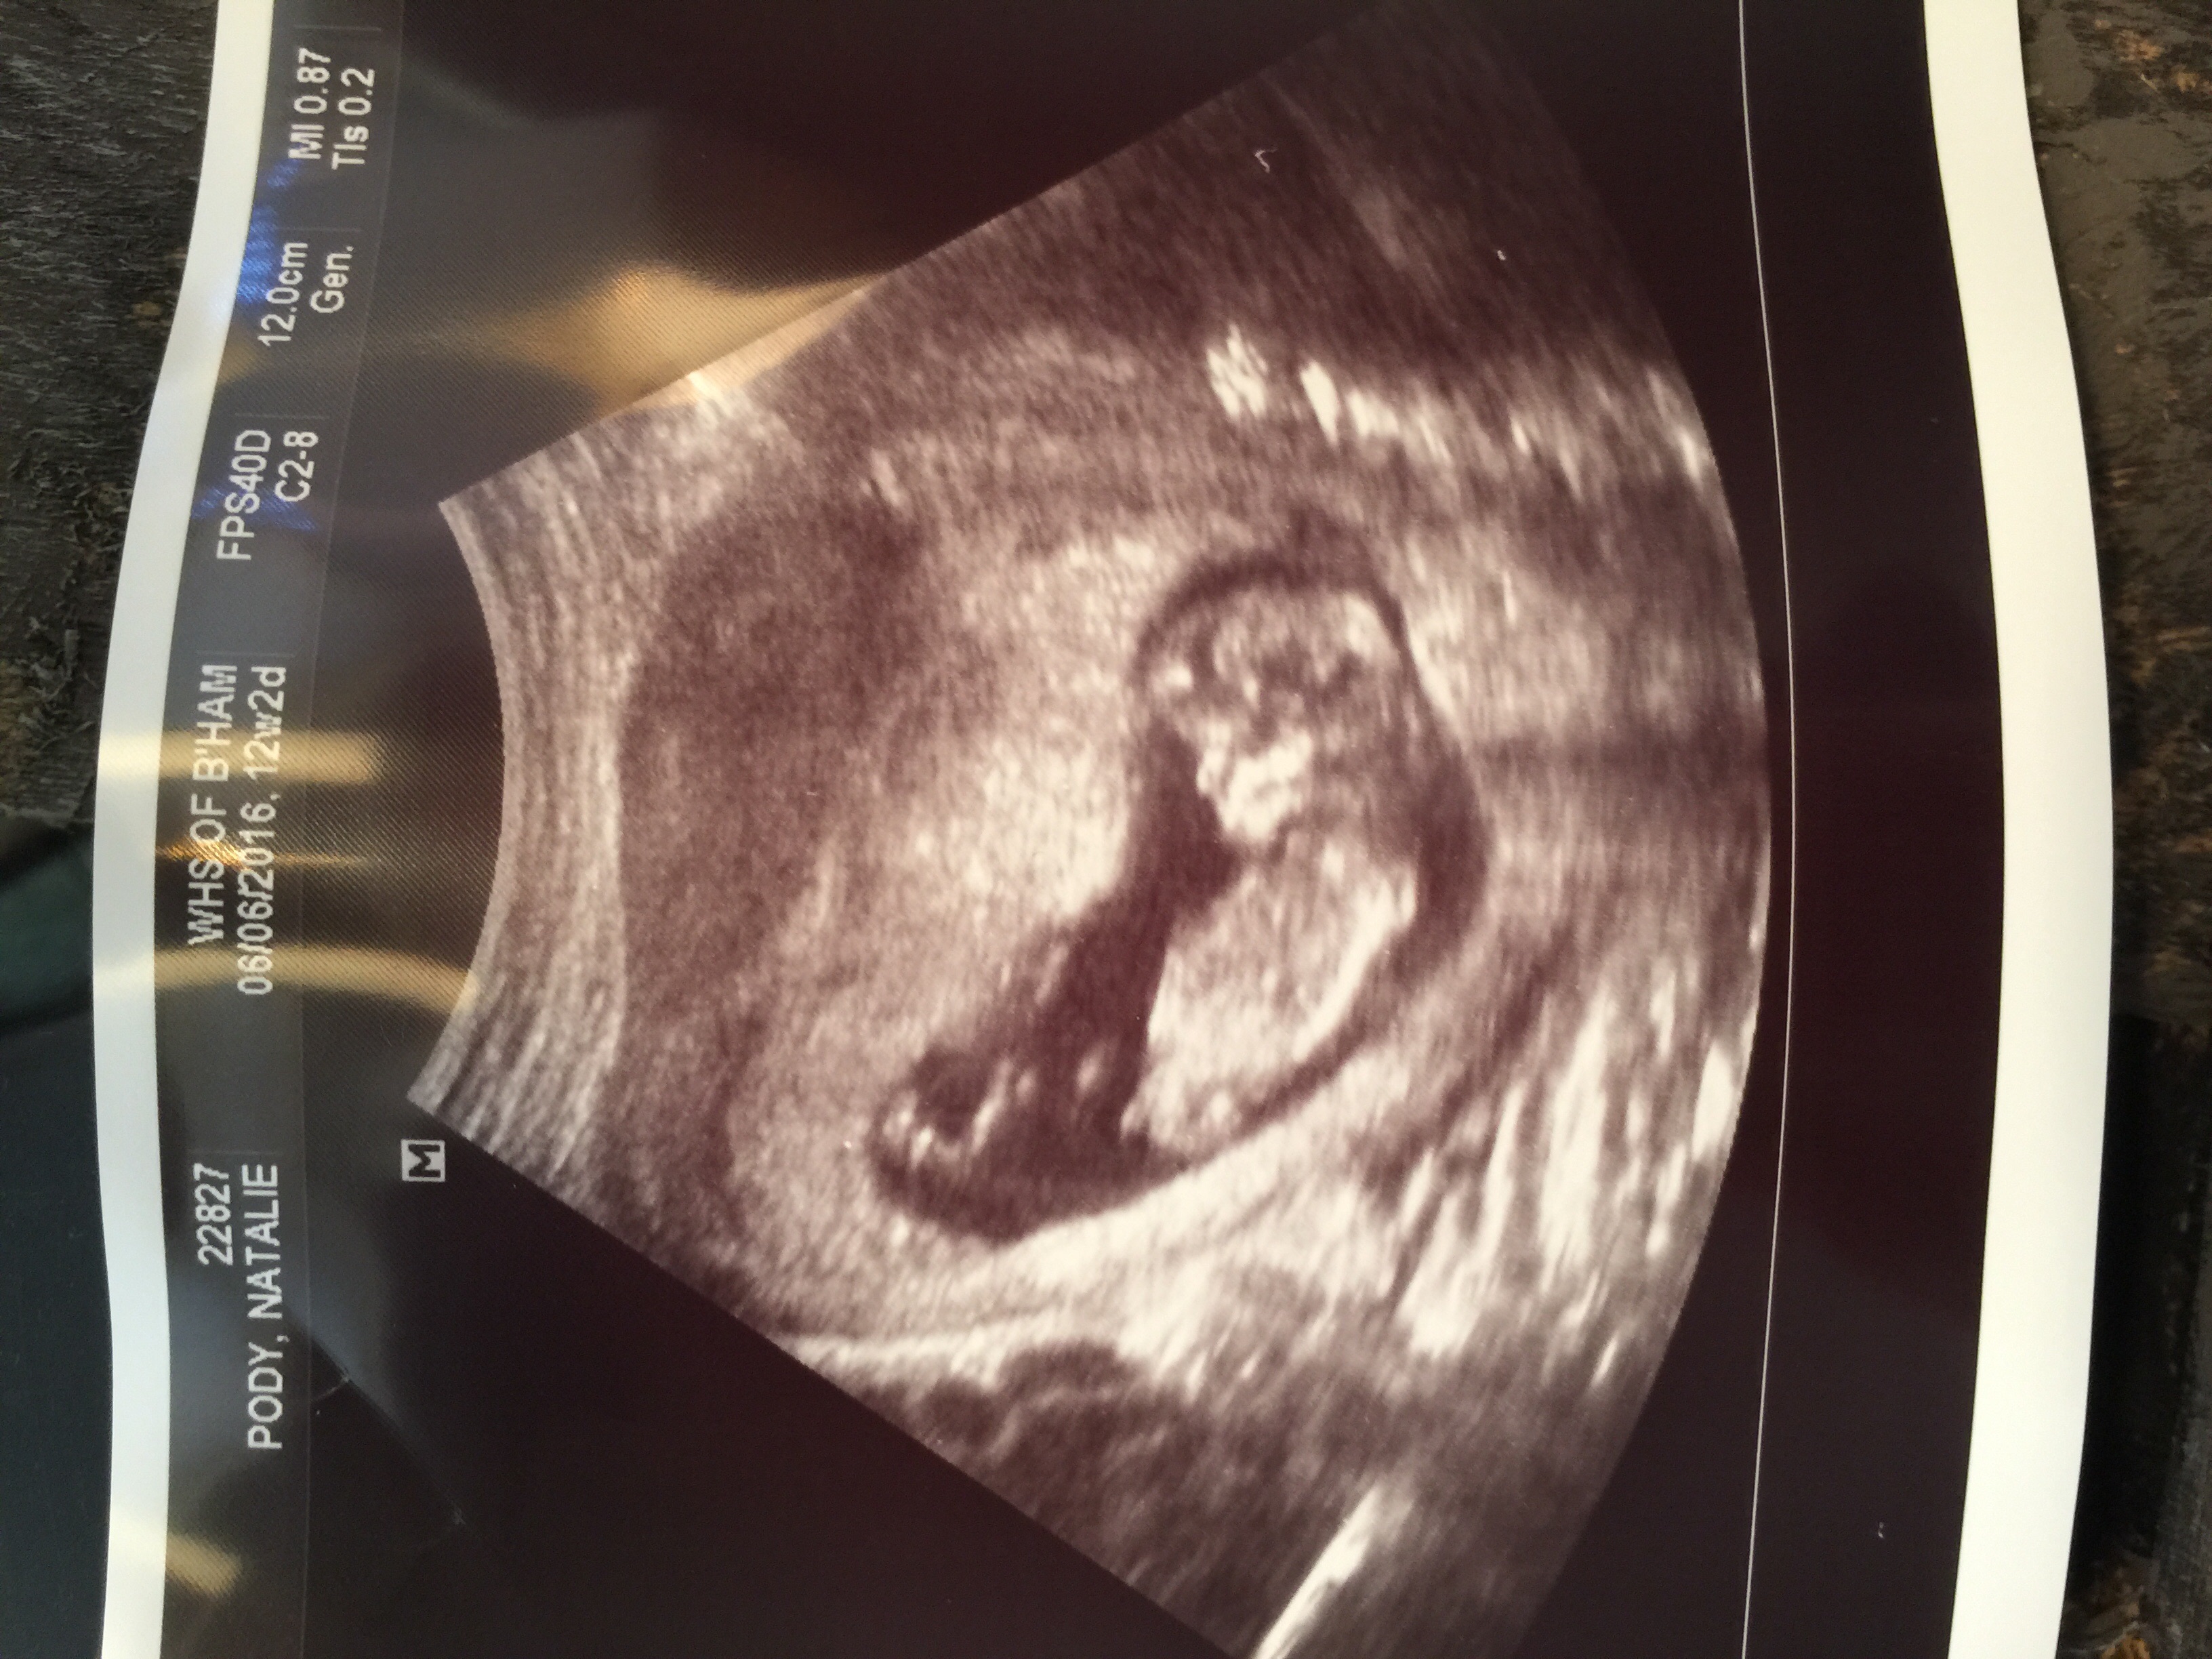

If this is even a nub!lol I'm only 12 and 2 so it's very early but just for fun! I do not care either way so share your guesses! She looked between the legs and didn't see anything but this looks like a blue nub to me. Attachment 28644

Another shot Attachment 28645

That on its belly in the first pic is the umbilical cord, correct? If that's a nub my husband will be so proud!hahaha